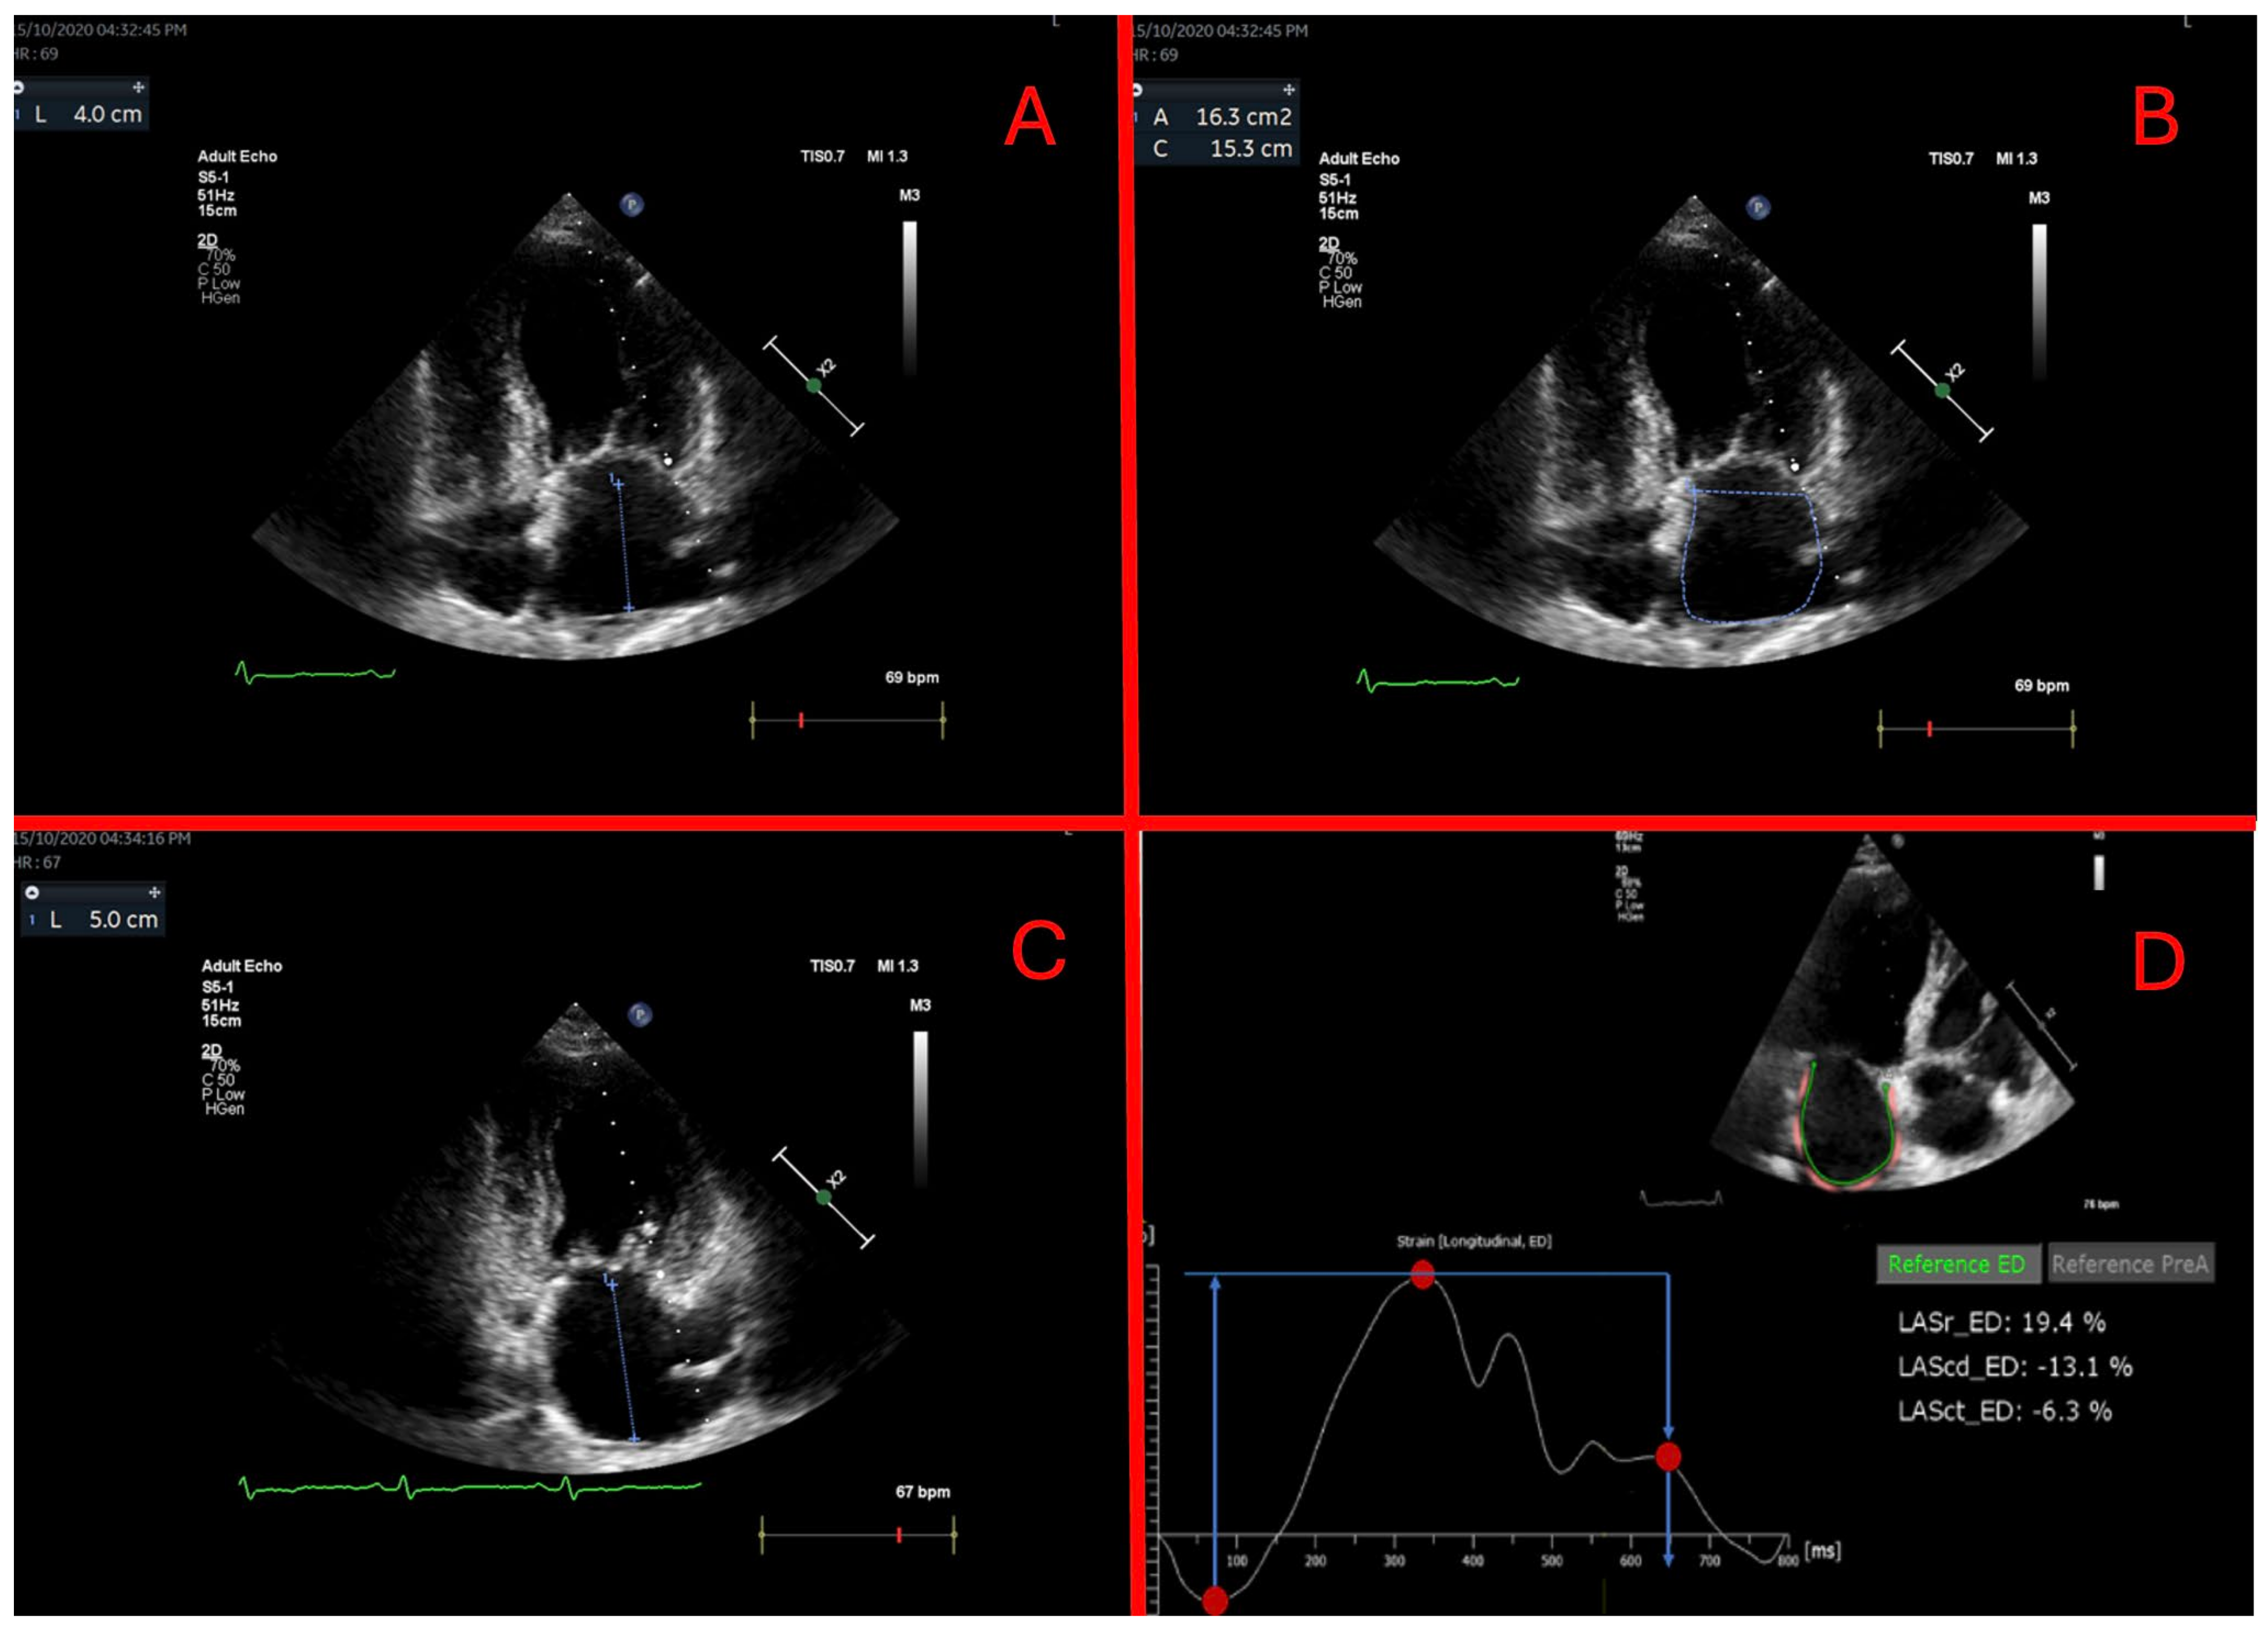

2.2. Echocardiography

2.3. Left Atrium Analysis